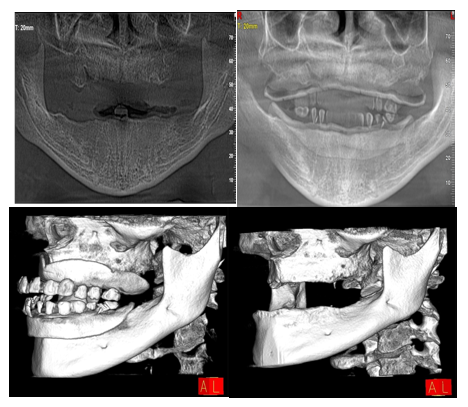

Radiographic and Digital Planning

Digital imaging played a central role in guiding the treatment protocol. Cone-Beam Computed Tomography (CBCT) was used to evaluate:

• -  Residual ridge volume and bone quality

• -  Relationship of anatomical landmarks (maxillary sinus, mandibular canal)

• -  Feasibility of parallel implant placement

Digital mock-ups and software-based planning ensured:

• -  Correct vertical dimension of occlusion (VDO)

• -  Ideal anterior-posterior tooth projection

• -  Harmonized smile line and lip support

This digitally guided approach helped predefine implant trajectories and prosthetic contours, minimizing intraoperative variability and supporting predictable esthetic outcomes.

Figure 1: Preoperative treatment plan assessment and simulation xray.